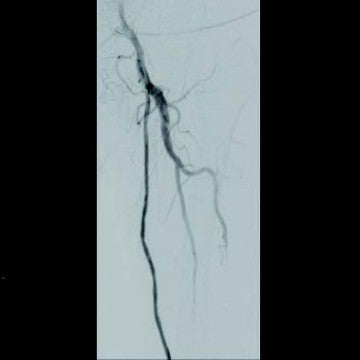

[治療] 右総大腿動脈(common femoral artery:CFA)を逆行性にエコーガイド下に穿刺。山越えで左 CFAまで6 Frガイディングシースを進めた。造影で左SFA起始部付近からベアステント遠位端のやや中枢側まで、TOSAKA分類3のISO病変があることを確認した。ところどころ病変が硬く、0.014 inchガイドワイヤーの先端2.8 gと先端12 gを順次使用して閉塞部位を突破した。PTAバルーン4 mm × 250 mmで前拡張したのち、病変部をカバーするように左SFA末梢側から左SFA起始部にかけてバイアバーン® ステントグラフト6 mm × 250 mmと6 mm × 100 mmを留置し、閉塞したベアステントをフルカバーした。バルーン5 mm × 220 mmで後拡張を実施、血管内超音波(IVUS)と造影で病変部の良好な拡張、血流を確認し手技を終了した(図3)。足関節上腕血圧比(ABI)は0.68から0.92に改善した。さらに6年が経過し、間欠性跛行の再燃があり、ステントグラフトは開存していたが(図4-1)、さらに末梢の膝窩動脈での石灰化プラークによる閉塞病変(図4-2)が原因と考えられた。アテレクトミーデバイスとDCBで膝窩動脈病変を治療して症状は消失した。run offが不良であったにもかかわらず、中枢側のステントグラフトが6年間開存していたことは特筆すべきことである。同患者については現在まで15年にわたり経過をみているが、経年的に動脈硬化が進んでおり、通常のステントやバルーンでの治療部は再治療を繰り返している。その中でステントグラフトを留置した長区間ISO病変は6年間開存を保っていたというのは、物理的に内膜過形成をシャットアウトするステントグラフトでしかみられない現象であると思われる。ISO病変に対するバイアバーン® ステントグラフトの使用が保険適用されるようになったことは、血管内治療医や患者に福音をもたらしたのではないだろうか。